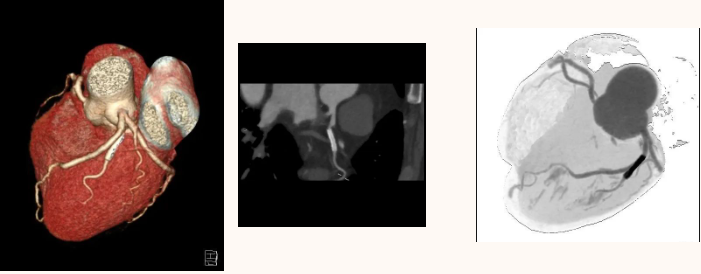

CT 血管造影(CTA),即 CT 血管成像,是一种利用计算机三维重建方法合成的非创伤性血管成像技术,可以在没有创伤的情况下,很好地了解身体中血管的情况。具有时间短、无创、特异性和敏感性高,时间和空间分辨率高等特点,能全方位显示出血管病灶,对于经其他检查已经明确患有血管疾病,需进一步了解病情严重程度具有重要的意义。

通过 CT 血管成像,可显示动脉病变,如血管闭塞、动脉瘤及夹层动脉瘤、血管畸形、血管损伤、心脏冠状动脉病变等。可进行冠心病 CT 筛查,冠心病术前、术后评估,脑卒中一站式检查,灌注成像等。